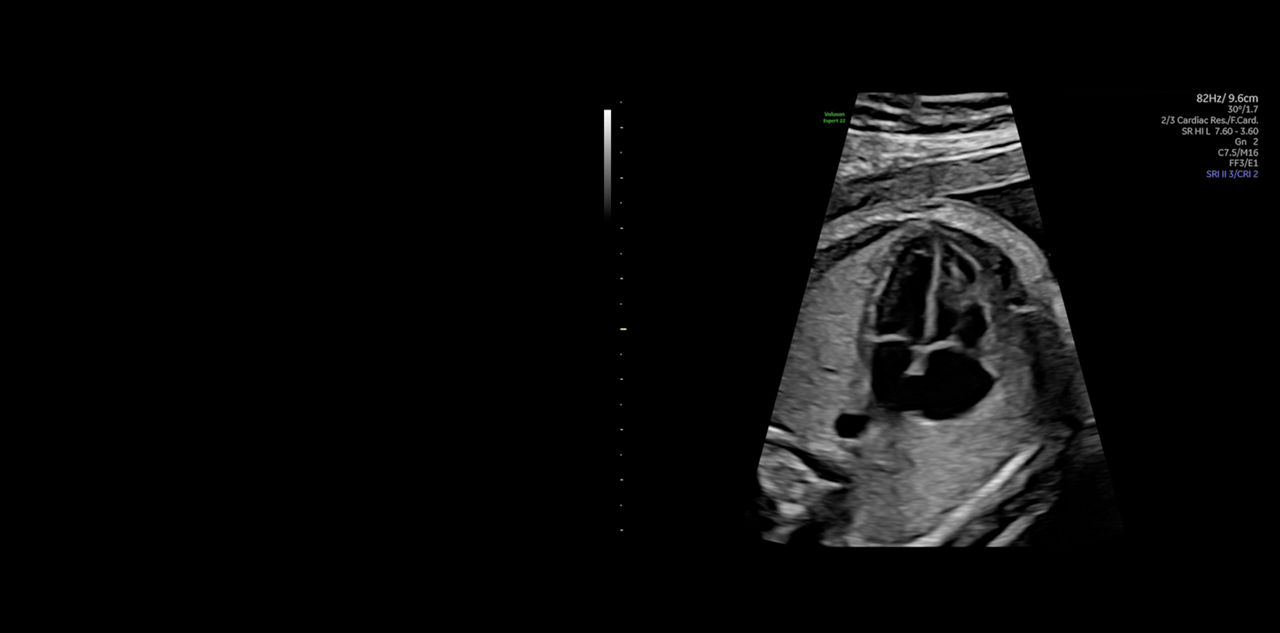

FETAL HEART EVALUATION

Get to the Heart of the Matter

Identifying fetal cardiac abnormalities earlier means you can intervene sooner, plan for delivery, and potentially improve outcomes. The Voluson Expert 22 provides a full solution of progressive tools, to help distinguish the tiniest structures with stunning clarity to provide patient answers faster.